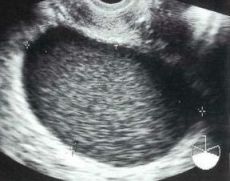

<エコー>

チョコレート嚢胞で特に有用です。96回医師国家試験D39でも出題されています。